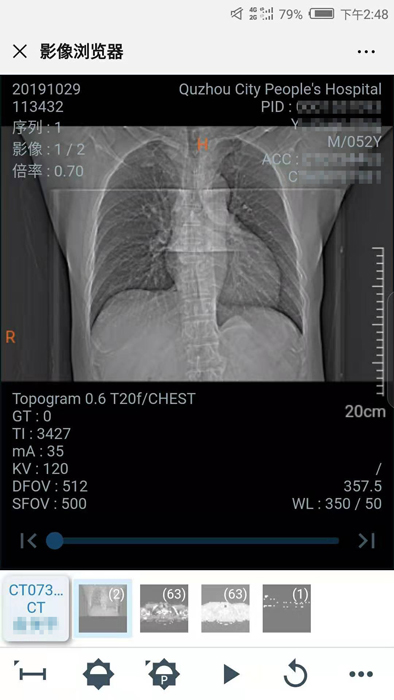

10月29日晚,我院向住院患者推行數(shù)字影像服務(wù),云膠片正式上線!點(diǎn)點(diǎn)手機(jī)就能查看片子不限次數(shù)瀏覽影像……方便、省錢、精準(zhǔn)、環(huán)保,“云影像”服務(wù)平臺(tái)讓您看病更省心。

“影像圖片十分清晰,還能根據(jù)自己的需求放大縮小,這可比拿著膠片到處跑省心多了!”

10月30日,住院患者俞先生收到一條短信提醒“【云影像】衢州市人民醫(yī)院提醒您,俞先生的CT報(bào)告已完成……”俞先生隨即點(diǎn)擊手機(jī)上的瀏覽鏈接,輸入身份證后六位,驗(yàn)證完成,短短幾秒鐘,躺在病床上也能查看到自己的CT電子報(bào)告和影像,俞先生直呼神奇。

“醫(yī)院面向住院患者全面推行檢查檢驗(yàn)結(jié)果電子化,互認(rèn)共享,全面提供網(wǎng)上查詢、移動(dòng)推送等服務(wù),‘云影像’平臺(tái)的運(yùn)行就是深化‘最多跑一次’改革要求的又一新舉措?!贬t(yī)院信息處工作人員介紹,“ ‘云影像’是儲(chǔ)存在云端的病人醫(yī)學(xué)影像檢查信息,包括檢查報(bào)告、電子膠片及供專業(yè)影像科醫(yī)生診斷瀏覽的全部醫(yī)學(xué)數(shù)字原始影像。放射檢查報(bào)告完成后,醫(yī)院會(huì)同步發(fā)送提醒短信到患者的手機(jī)上,只要點(diǎn)擊短信上的鏈接就可第一時(shí)間獲取‘云影像’及報(bào)告。使用‘云影像’查看檢查報(bào)告,解決了排隊(duì)取片、復(fù)診帶片的煩惱,縮短了就醫(yī)時(shí)間,讓老百姓看病得到實(shí)實(shí)在在的方便?!?